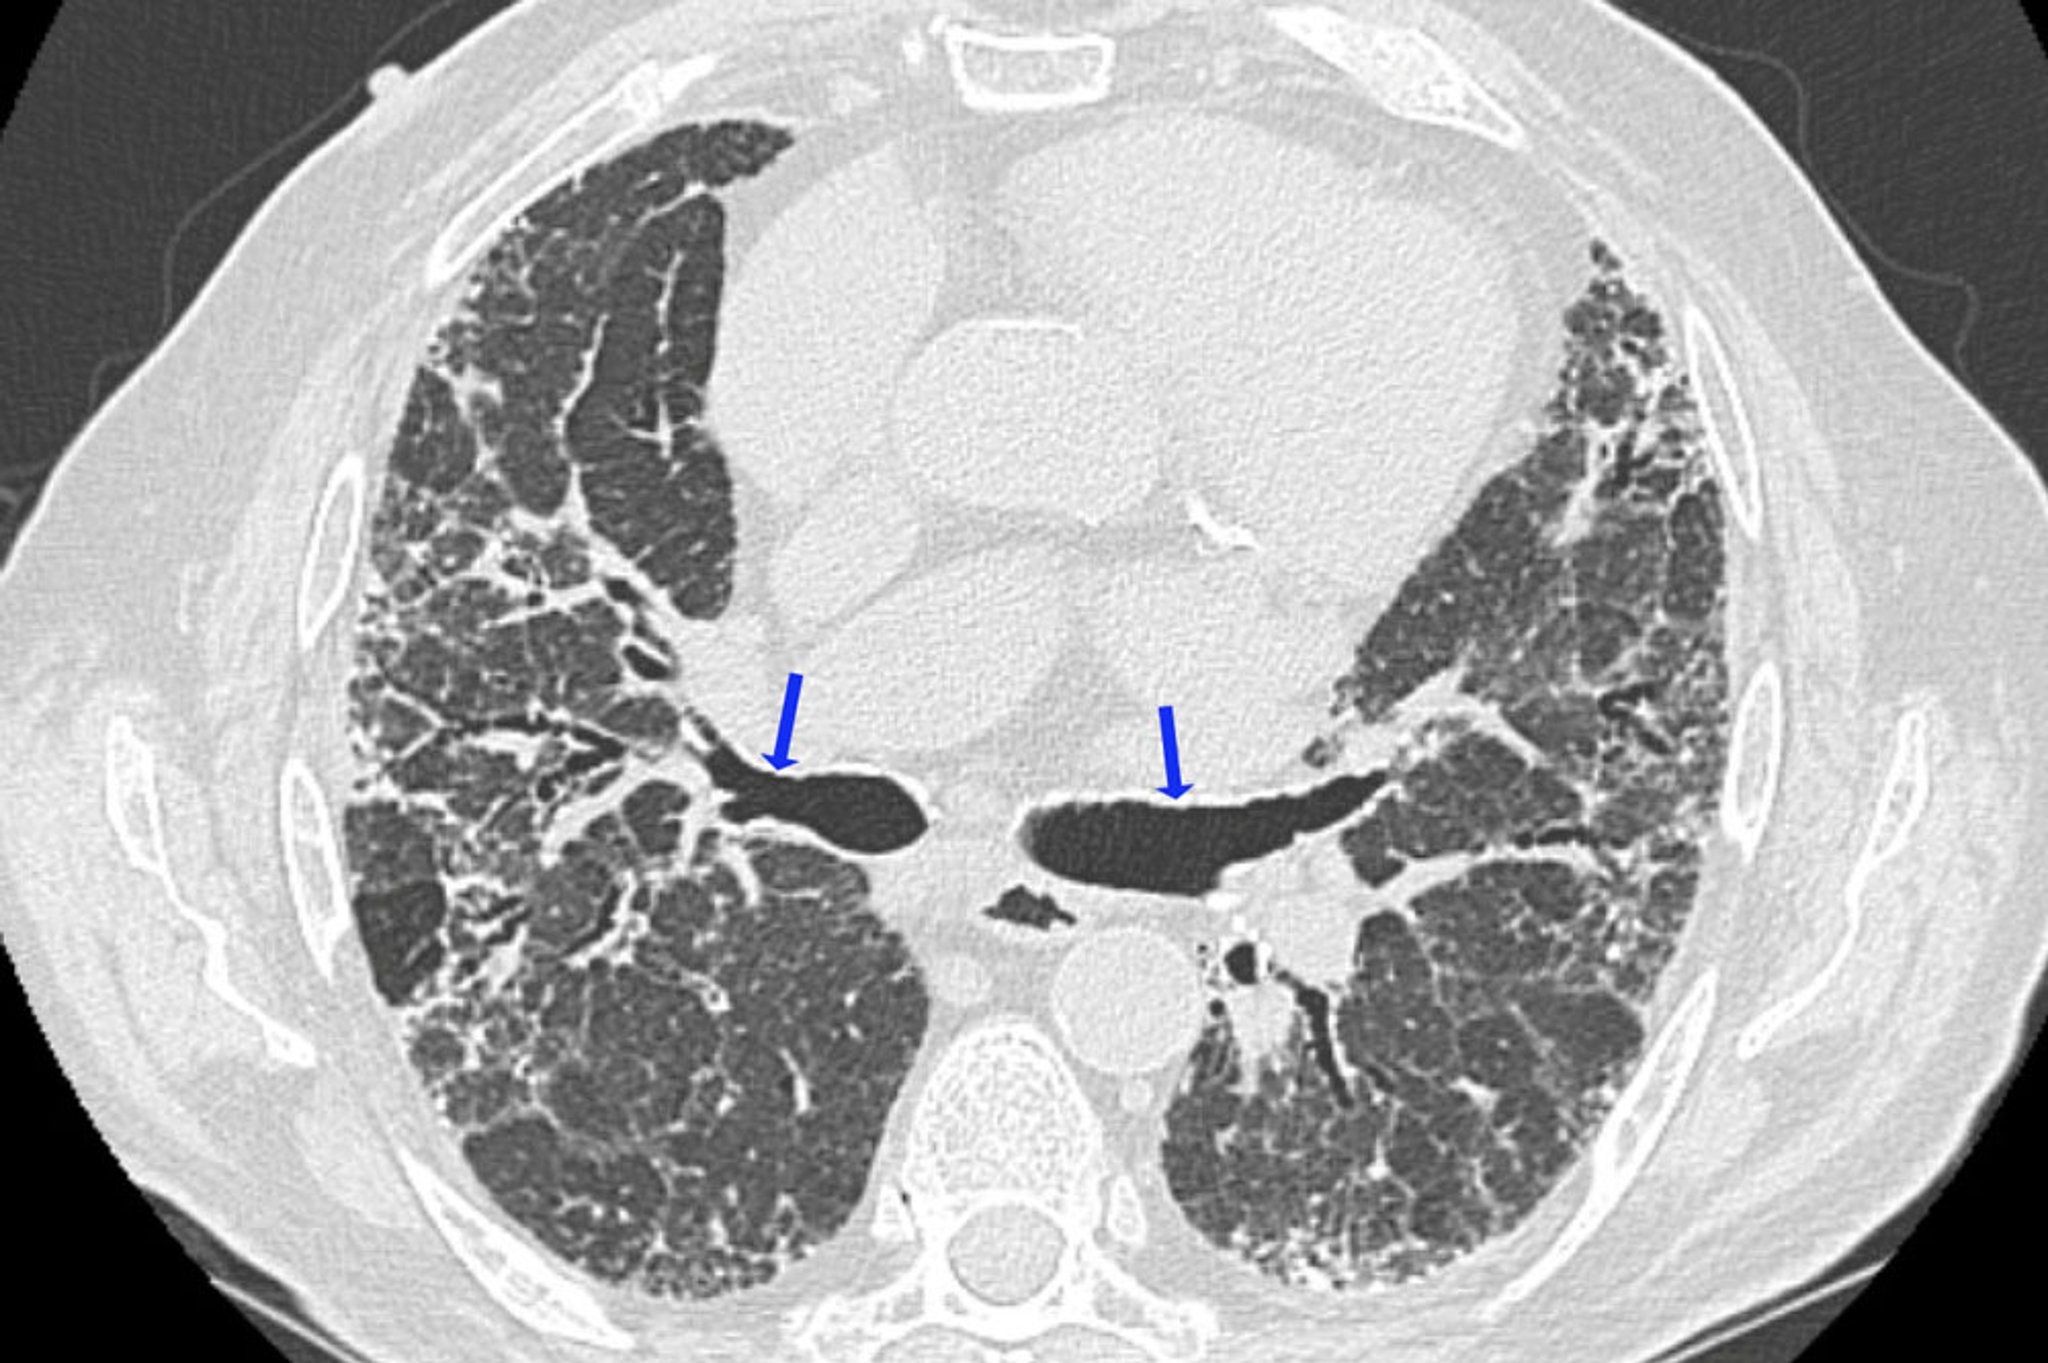

过敏性肺炎

高分辨率CT显示纤维化的表现,包括不规则网状影和牵引性支气管扩张(箭头所示)。肺密度降低的区域与气道阻塞的区域一致。这些表现的组合提示过敏性肺炎。

图像由医学博士、MAS Joyce Lee 提供。